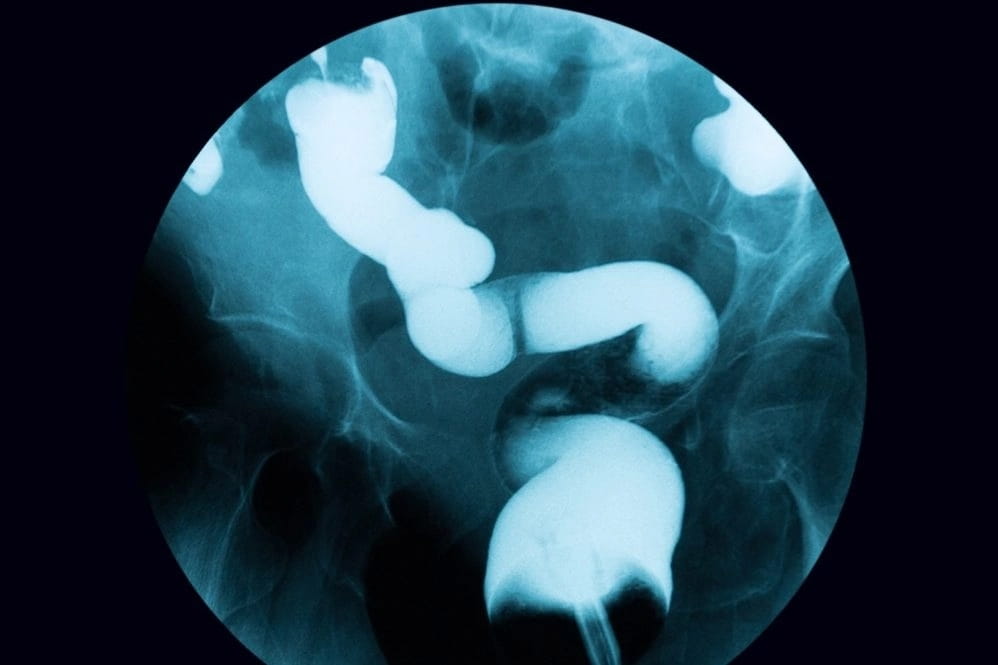

Непаразитарные кисты могут быть врожденными, а могут возникать как осложнения некоторых других заболеваний. Для их диагностики используют методы компьютерной томографии и ультразвуковые исследования.

Диагностика причин болезненных ощущений селезенки основана на оценке ее размера, параметров гемодинамики, истории травмы или других заболеваний и других сопутствующих симптомов. Пальпация нижней границы селезенки может помочь оценить степень увеличения.

Врач может подтвердить проблемы c селезенкой на основании одного или нескольких из этих исследований:

- Анализы крови, чтобы проверить количество эритроцитов, лейкоцитов и тромбоцитов

- Ультразвуковая или компьютерная томография (КТ) для определения размера органа

- Магнитно-резонансная томография (МРТ) для отслеживания кровотока через селезенку.

- Рентген — позволяет увидеть увеличение размеров селезенки, желчного пузыря, желудка, надпочечника, почки. Перед процедурой в брюшную полость пациента вводится кислород для улучшения информативности исследования.

- Ультразвуковое исследование органов брюшной полости.